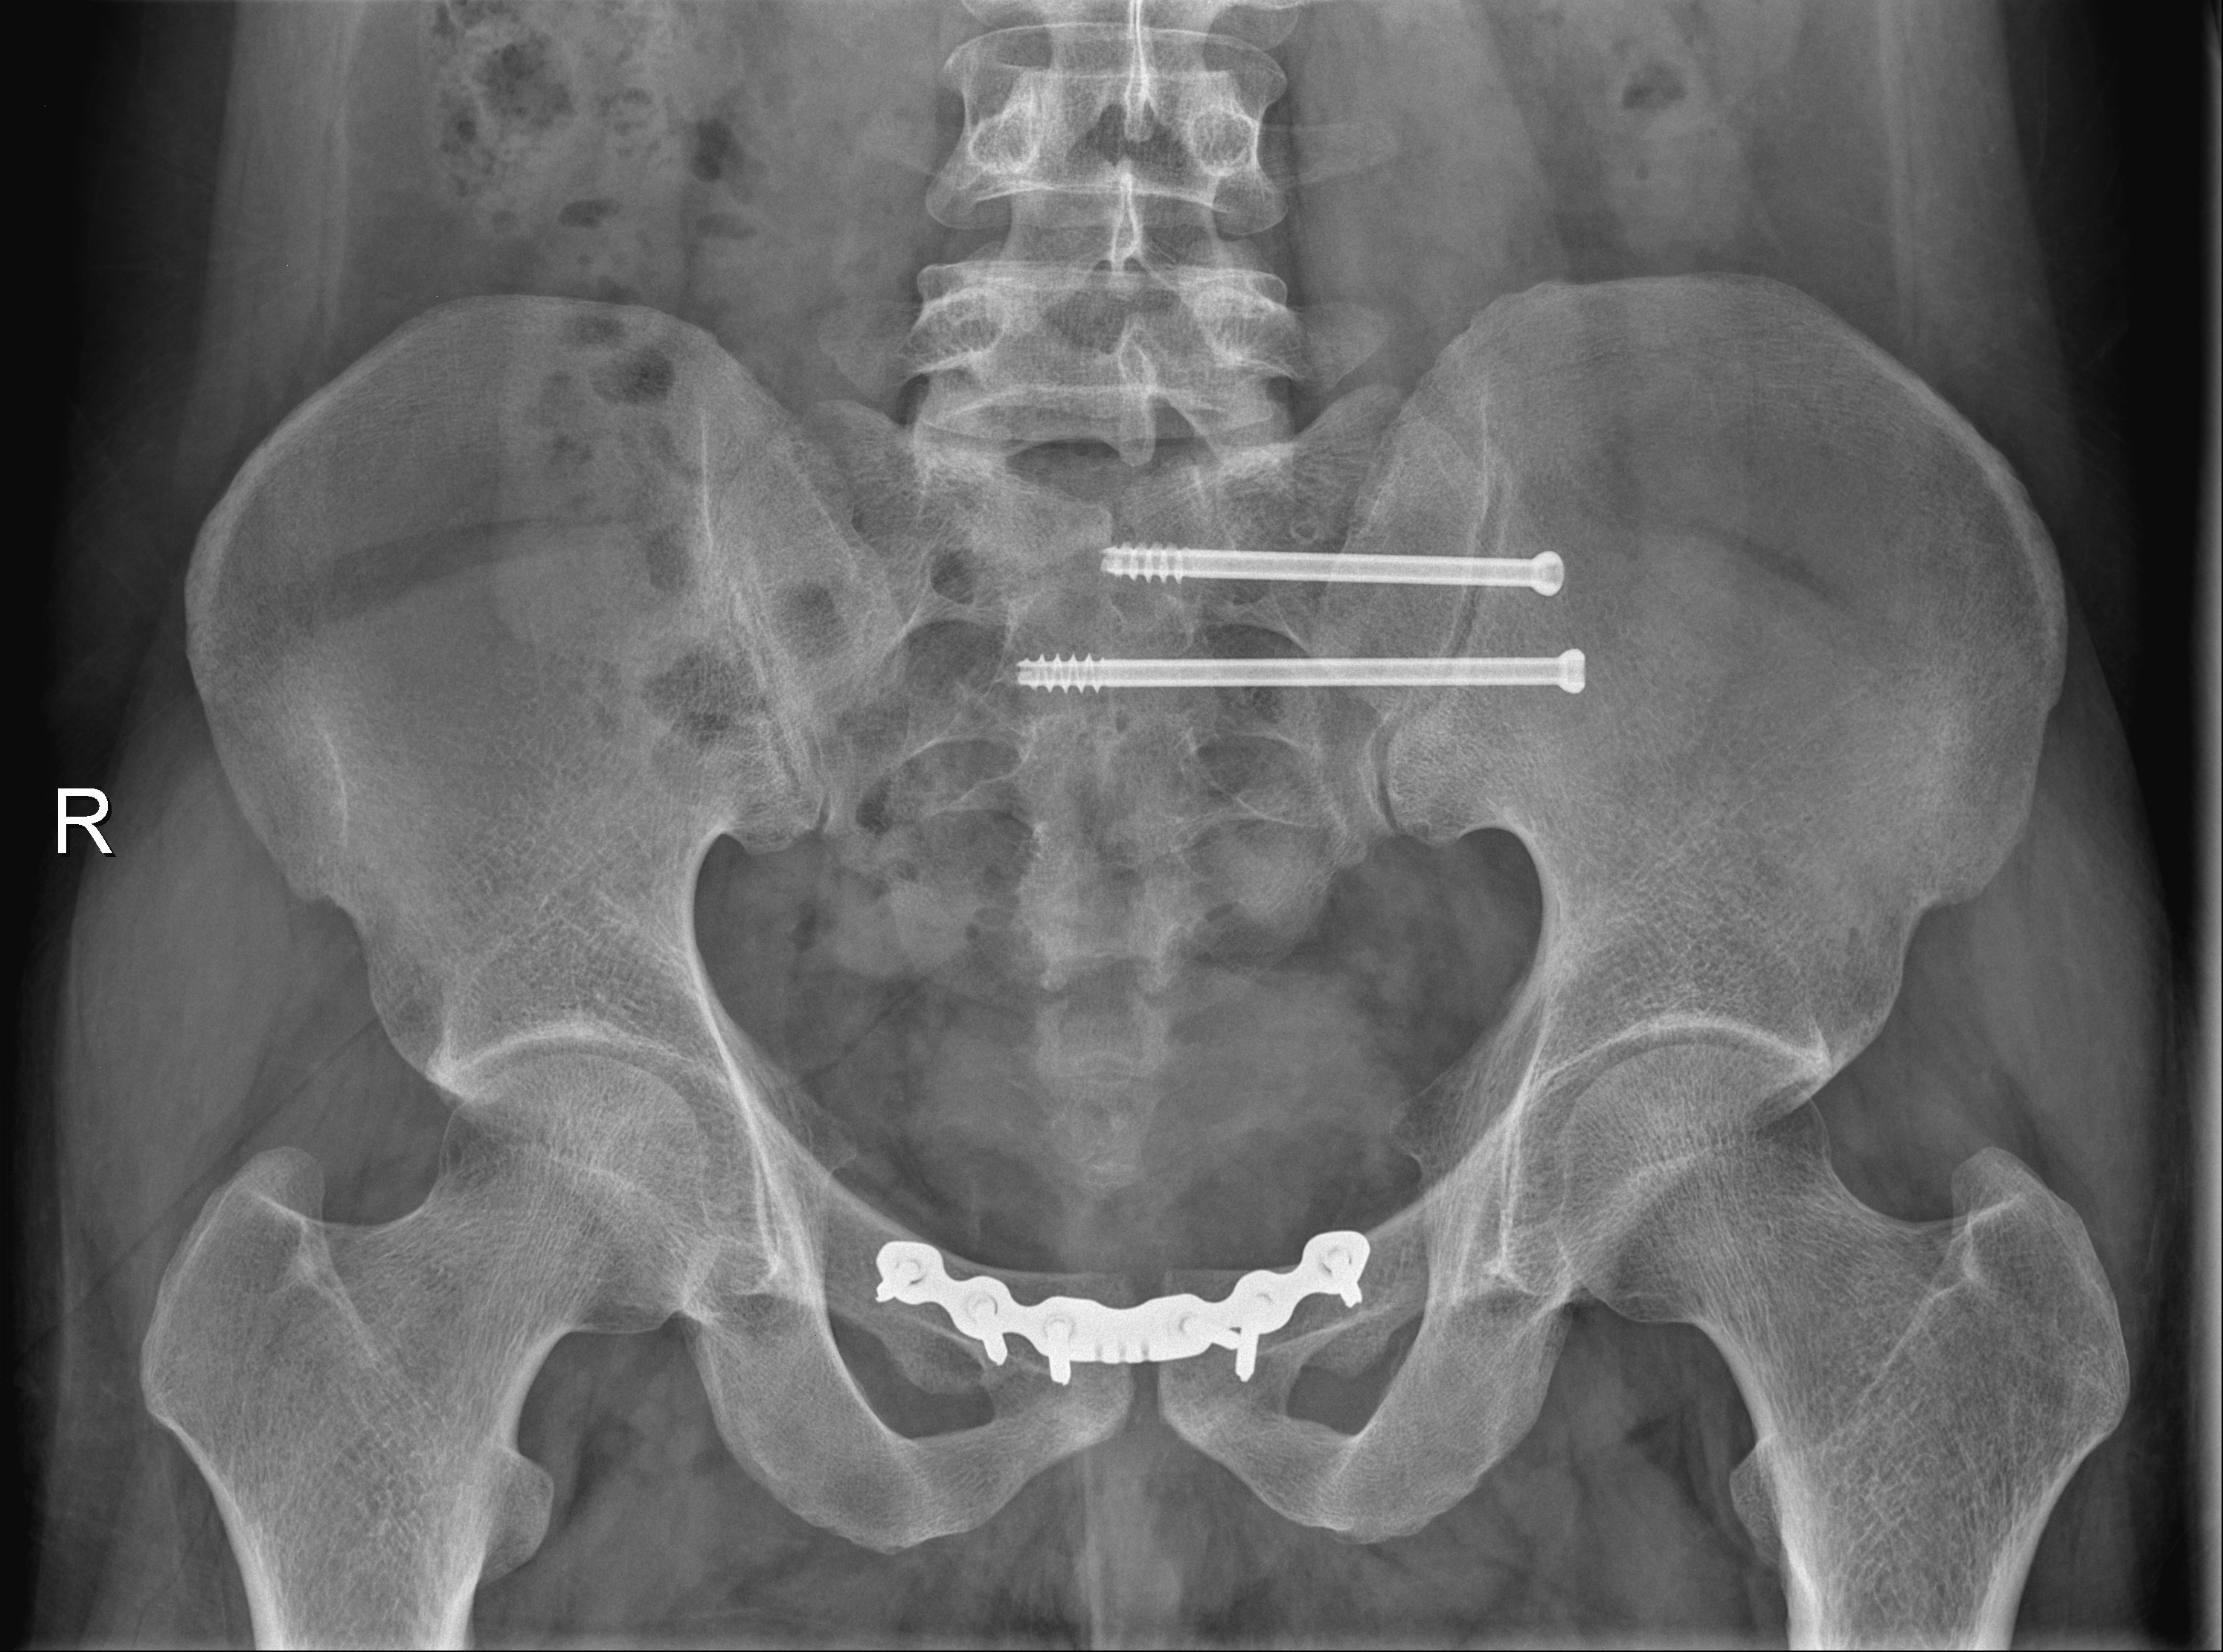

术后

6月12日晚北京遭遇大风天气,一名外来务工人员不幸从约六层楼高处坠落,生命垂危。潞河医院接到120急救电话,医疗部了解相关情况后迅速启动创伤救治绿色通道,确保患者得到及时救治。经过初步检查,患者被诊断为合并创伤性休克、骨盆粉碎性骨折、多发肋骨骨折、血气胸,并紧急收入重症监护室进行生命支持治疗。为提供最佳治疗方案,第二天上午医院迅速召集了多学科专家团队进行会诊。在医疗部指挥下,由骨中心主任刘亮、创伤骨科主任王雪飞牵头,专家们针对患者病情进行了全面细致的分析、评估和讨论,制定了详尽的手术计划。患者因骨盆粉碎性骨折导致失血性休克,创伤严重程度评分高达25分,属于严重多发创伤。在此情况下,对骨盆骨折进行快速有效的手术固定止血成为关键。得益于多学科团队的紧密合作和高效沟通,患者在下午被紧急送进手术室。在胸外科、麻醉科、重症监护室等多个科室的共同努力下,借助骨科机器人的精准操控,创伤救治团队迅速完成了对不稳定骨盆骨折的闭合复位和微创螺钉内固定手术。骨科机器人的应用显著缩短了手术时间,提高了手术效率。